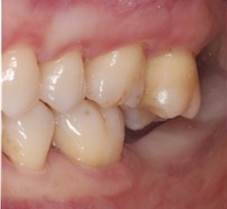

Se presenta a consulta una paciente de género femenino de 56 años, que su motivo de consulta es “necesito un implante”. En el interrogatorio de la historia clínica la paciente no presenta antecedentes patológicos ni no patológicos, por lo que fue clasificada como ASA I11. A la exploración clínica se observó la ausencia del segundo molar inferior derecho (4.7), el cual, refiere la paciente, perdió por caries. A su vez, se encontró la extrusión del molar antagonista (1.7) hacia el área a rehabilitar e inflamación gingival inducida por placa (Fig. 1).